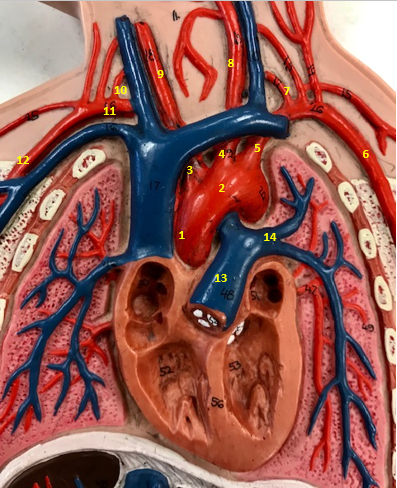

Aorta

Name #2

Brings blood out of left ventricle

Function of aorta

Brachiocephalic artery

Name #3

Supplies oxygenated blood to right arm shoulder neck and head

Function of brachiocephalic artery

Left common carotid artery

Name #4

Supplies oxygenated blood to left neck and head

Function of left common carotid artery

Left subclavian artery

Name #5

Supplies oxygenated blood to left arm shoulder

Function of left subclavian artery

Left axillery artery

Name #6

supplies blood to left armpit and upper limb

Function left axillary artery (6)

Left vertebral artery

Name #7

Supplies blood to brain and spinal cord

Function of left vertebral artery (7)

Left common carotid artery

Name #8

Supplies blood to left neck and head

Function of left common carotid artery (8)

Right common carotid artery

Name #9

Supplies oxygenated blood to right neck and head

Function of right common carotid artery (9)

Right vertebral artery

Name #10

Supplies blood to brain and spinal cord

Function of right vertebral artery (10)

Right subclavian artery

Name #11

Supplies blood to right arm and shoulder

Function of right subclavian artery

Right axillery artery

Name #12

Supplies blood to right armpit and upper limb

Function of right axillery artery (12)

Pulmonary trunk

Name #13

Bring blood out of right ventricle to lungs

Function of pulmonary trunk (13)

Left pulmonary artery

Name #14

Bring blood to left lung

Function of left pulmonary artery (14)